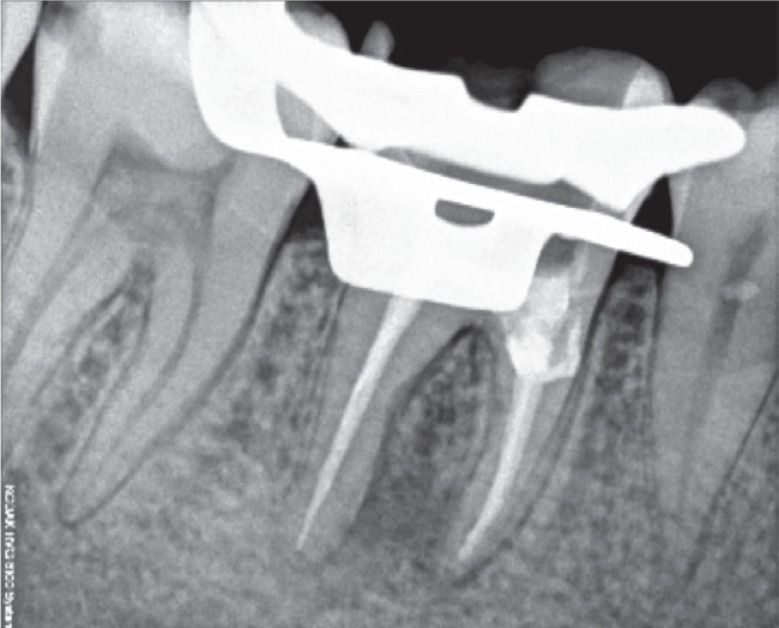

Figure 1). Radiographic analysis revealed a periapical radiolucent lesion around the mesial and distal root of tooth #46, and the periradicular dentin at the coronal third of the mesial root was compromised as a result of the poor endodontic access cavity (

Figure 2Preoperative radiograph revealing a periapical radiolucent lesion in the region of the mesial and distal root of tooth #46, as well as compromised periradicular dentin at the coronal third of the mesial root due to a poor endodontic access cavity.